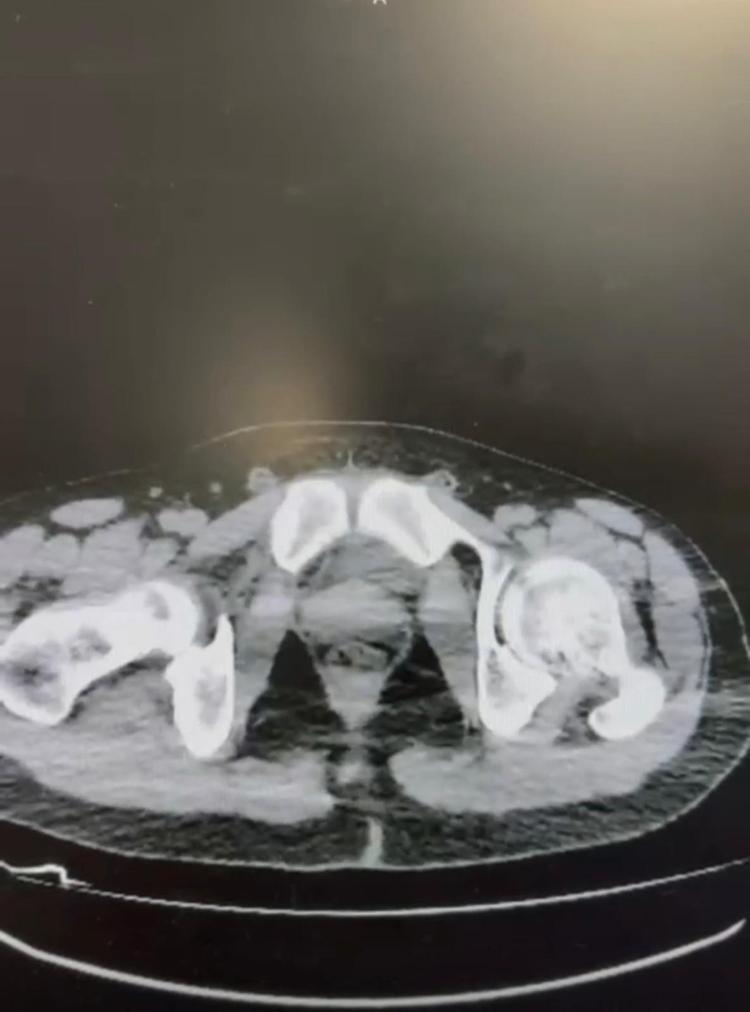

Nevşehir Cumhuriyet Başsavcılığı koordinesinde İl Emniyet Müdürlüğü Narkotik Suçlarla Mücadele Şube Müdürlüğü ekipleri, S. B. ve O. R.’nin, ‘Yutma yöntemi’ ile kentte uyuşturucu getireceği bilgisine ulaştı. Ekipler, düzenlenen operasyonla 2 şüpheliyi yakaladı. Yapılan aramalarda hassas terazi, uyuşturucu sevkiyatında yutma yönteminde kullanılan materyaller, uyuşturucu madde ticaretinden elde edilen 20 bin 210 TL, bin 320 avro ve 10 dolara el konuldu. Gözaltına alınan S.B. ve O.R., muayene edilmek üzere Nevşehir Devlet Hastanesi’ne getirildi. Röntgeni ve ultrason çekiminde, şüphelilerin midelerinde kapsüller tespit edildi. Yapılan müdahaleyle 2 şüphelinin midesinden 101 kapsül halinde 722 gram metamfetamin çıktı. Adliyeye sevk edilen S.B. ve O.R., tutuklanarak cezaevine konuldu.